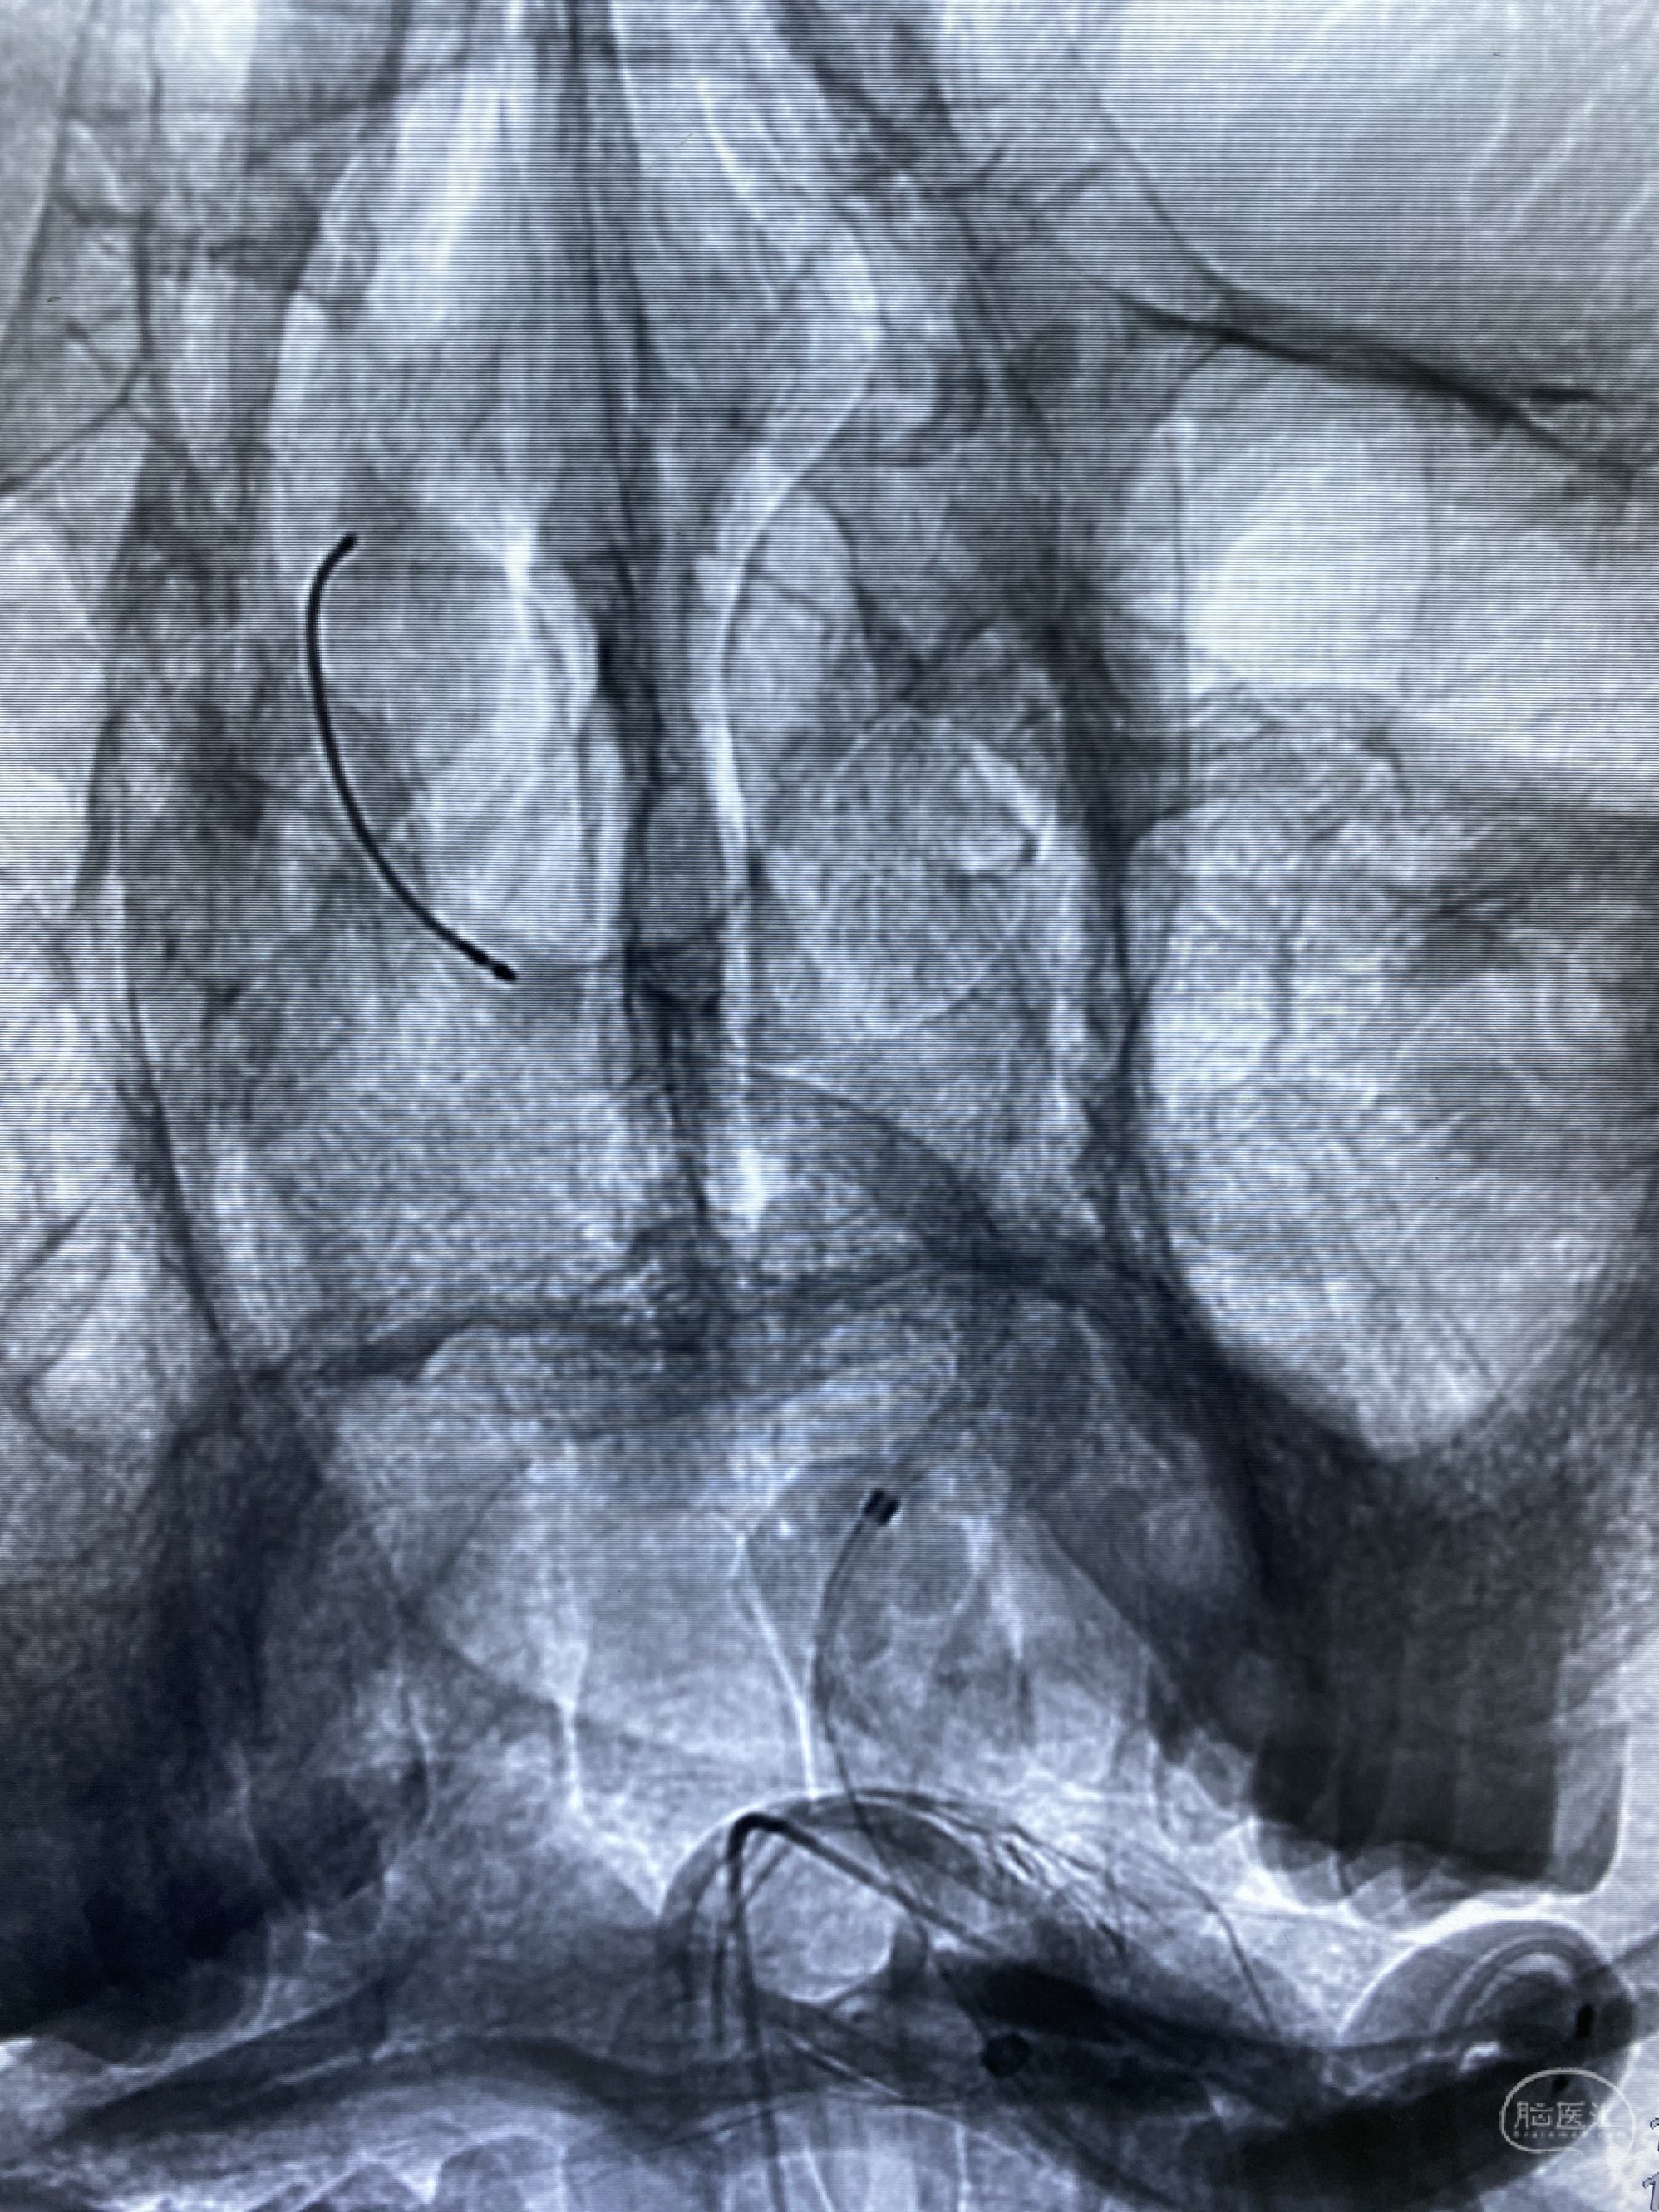

椎动脉颅内段多发夹层动脉瘤伴载瘤动脉狭窄pipeline flex植入

今日手术,TJG,M62Y,一期左侧颈动脉狭窄支架植入,二期椎动脉V4段多发夹层动脉瘤伴狭窄,常规支架辅助栓塞方法复杂又危险,血流导向装置植入快捷又安全。南阳市中心医院神经内科脑血管病介入团队pipeline flexFD植入两人导师资格。